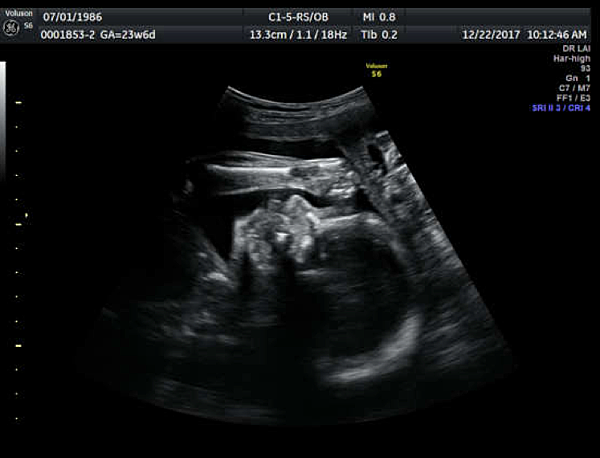

21W5D 到由劉醫師轉介的孕兒診所照高層次超音波,孕兒診所小小間的,但很溫馨,裡面很溫暖,大家也都非常親切~

我們早上10:10照到大概10:40,剛開始照的時候,寶寶就把雙手打開,乖乖的讓他們數手指,操作師說寶寶很棒,因為大部份寶寶都會手握拳頭~

照的很快也很詳細,聽到每個部分都ok的時候,真的放心許多!只是寶寶躺得很舒服,照不太到更詳細的脊椎,操作師跟在後面觀看螢幕的賴醫師一直跟寶寶說:弟弟啊~翻一下~轉一下~!

但寶寶始終躺的舒服,醫師請我們先出去外面吃個糖果,走一走~過十分鐘後再進去照,還是一樣的姿勢~於是醫師請我們40分鐘後再回來~

我和Chris就跑去逛附近的菜市場,買了一些菜,也在那邊吃了麵,一邊跟寶寶喊話。

結果40分鐘後回去,寶寶還是維持那個姿勢躺得好舒服阿,醫師跟我們說,有的人為了照那個部位,一共來了三次~因為需要寶寶趴著,這真的要看運氣啊。

只好再找時間回去一趟了~但聽到其他部位一切正常,真是好棒好棒的消息,而且賴醫師說:你們的寶寶營養特別好哦!

因為實際週數21W5D,照出來有23W3D,寶寶614g~醫師還要我少吃點甜的~噗~其實我不愛吃甜食,我想都是媽媽給的滴雞精很營養!

滿23W這天又到孕兒診所回診,要照上次沒有照得太清楚的腰椎跟劍椎的部分,一躺下來寶寶還是維持上次那個仰躺的舒服姿勢~

噗...看來前一天對寶寶的喊話沒有奏效,醫生要我出去吃個糖果再進去照一次,結果還是一樣......

只好再等40分鐘,這天因為Chris工作忙,他就先去處理工作的事了,我在外面的公園散步晃晃,和寶寶喊話,買飯卷跟養樂多填填肚子,看吃吃東西寶寶會不會換姿勢~

結果第三次進去,寶寶還是躺得舒服~醫生說寶寶很堅持哦!然後我即將成為他們診所第三位要來第三次的媽媽~

但賴醫師很好,他說基本上他看過是可以的~只是因為他們照得更加仔細一些,所以第三次我可以選擇要不要來~

我們想說下次約下午時間看看,再照一次~